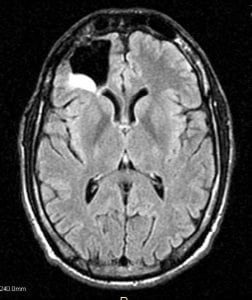

Recognizing that he needed access to a wide spectrum of specialized care, Moyles turned to the University of Colorado Cancer Center at UCHealth, where the scans every 90 days continued. In June 2015, a section of brain glowed brightly. Brain should show up gray.

Cancer had returned, and what had been an astrocytoma brain tumor had become a grade 4 GBM – a “terminator” brain tumor.

The images on the exam room screen differ, but share a common trait – blank space formerly occupied by a right frontal lobe. “New is on top, April is in the middle, and February is on the bottom,” Damek says, referring to the tiles of imager-sliced brain on the flat screen. Then the verdict.

“Your scan looks great.”

That is, there’s no hint of GBM this time, either. Moyles is visibly relieved, slouching as if anxiety had been propping him up.